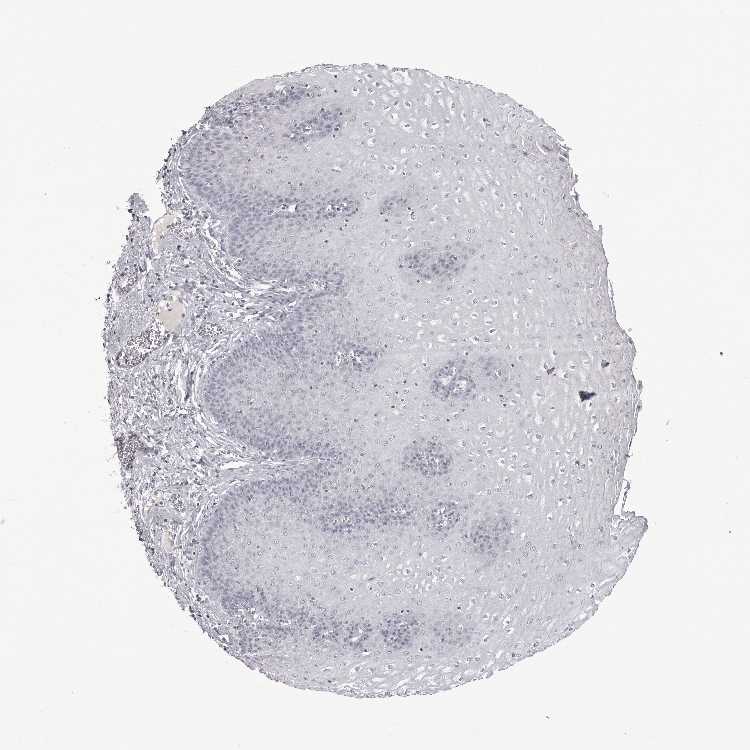

ESOPHAGUS - Antibody stainingi

Antibody staining in the annotated cell types in the current human tissue is reported as not detected, low, medium, or high, based on conventional immunohistochemistry profiling in selected tissues. This score is based on the combination of the staining intensity and fraction of stained cells.

Each image is clickable and will lead to virtual microscopy that enables deeper exploration of all samples and also displays staining intensity scores, fraction scores and subcellular localization as well as patient and tissue information for each sample.

Antibody HPA053417Antibody CAB022360

Squamous epithelial cells Not detectedNot detected